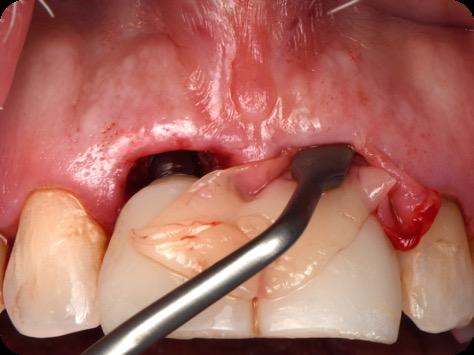

Fig 5. Central incisors extracted using minimally invasive protocol. Alveolar bone and gingival tissues were intact after extraction

Fig 6. BioHorizons Tapered Pro Conical implants of 3.8 x 15mm placed according to the plan.

Fig 12. Screw-retained provisional restoration placed into implants, with LPRF placed to protect graft material.

Fig 14. Clinical view at two days post-operative visit.

Fig 15. Clinical view at two days post-operative visit